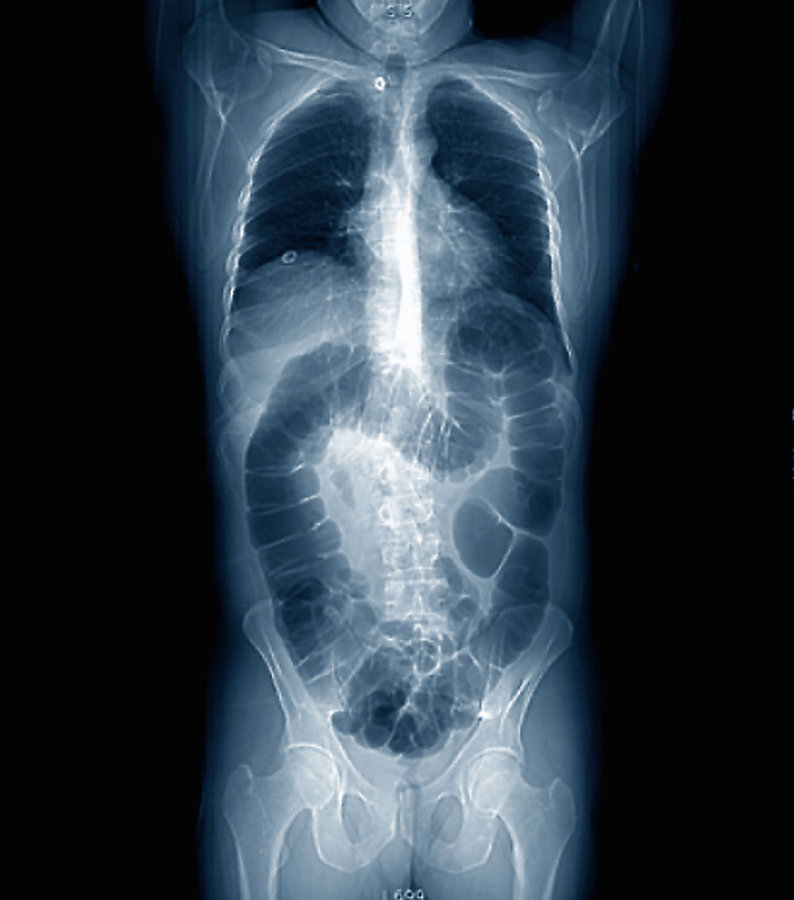

Während sich im CT noch kein Rezidiv bemerkbar macht, könnte die ctDNA dieses 54-Jährigen bereits darauf hindeuten. Während sich im CT noch kein Rezidiv bemerkbar macht, könnte die ctDNA dieses 54-Jährigen bereits darauf hindeuten. © Science Photo Library/Zephyr

Unauffälliges CT eines 54-jährigen Patienten. Unauffälliges CT eines 54-jährigen Patienten. © Science Photo Library/Zephyr